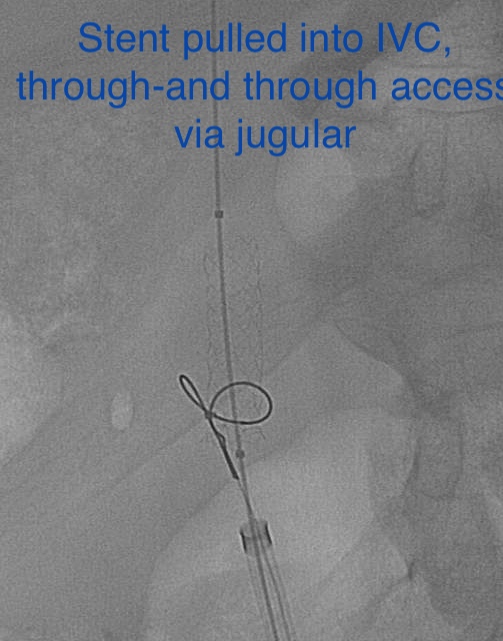

Pt presented to ED with CP, SOB. CXR shows embolized venous stent from OSH. Retrieved with 3 snares, 4 forceps, OR on standby,

@UABVascular help, 26F sheath, extra IR. Immediate symptom relief@SIRspecialists@SIRRFS@JVIRmedia#withoutascalpel#MIIPS#venous#embolize@uab_irpic.twitter.com/WpoUEt3P7z